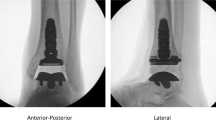

Processing of the CT files and three-dimensional solid reconstruction

An image of the right ankle joint of an adult man in a neutral position was obtained by computed tomography (CT) (64 slices, SIEMENS, USA). The thickness of the CT slice is 0.625 mm, and the bone threshold HU (Hounsfield Unit) is 0–1023. The image was input into the three-dimensional (3D) reconstruction software Mimics in the Dicom format to obtain a clear skeleton outline. After mask processing, the image was read in Geomagic (Geomagic, USA) using stereolithography (STL) format. Reverse engineering reconstruction was completed, and 3D graphics in the Initial Graphics Exchange Specification (IGES) file format was generated (Fig. 1).

The rationality of the model was verified by comparing the peak pressure of the tibiotalar joint contact and the contact area in the intact model with previous biomechanical experiments and FE models. Parameters under three walking gaits of 600 N bodyweight were consistent with previous studies [21, 24,25,26] with the same loading condition, as shown in Table 5.